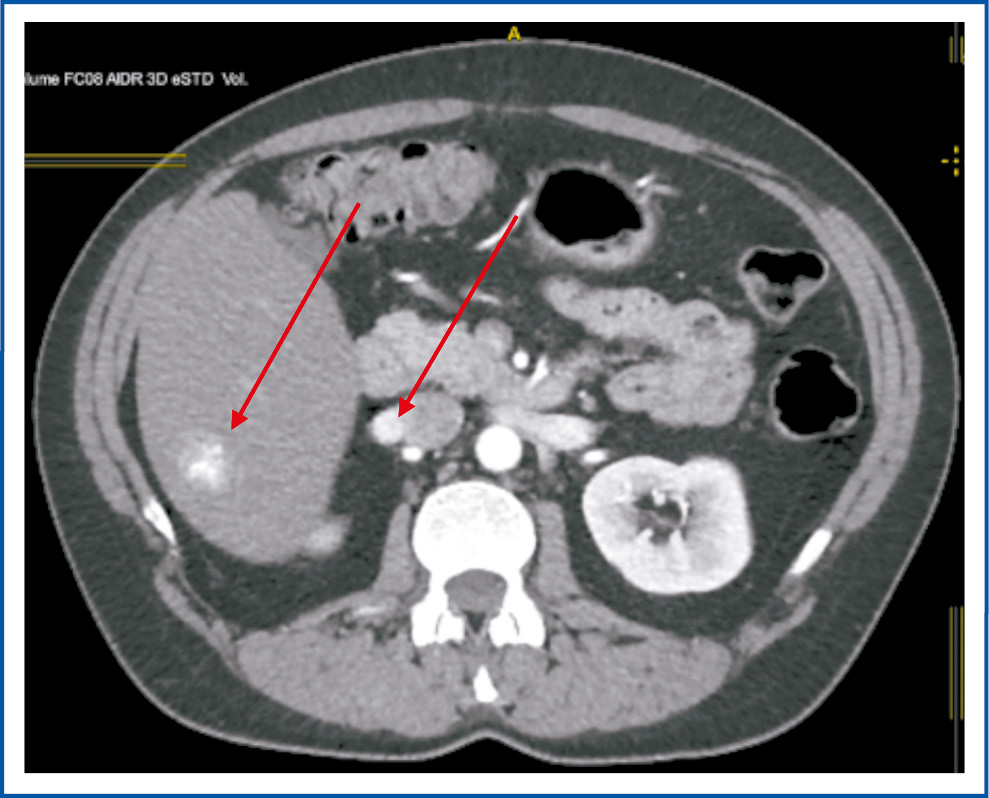

Через 6 лет, в мае 2022 г., пациентка снова обратилась в ГУЗ ОКОД г. Ульяновска, при осмотре – жалобы на боли в животе умеренного характера, слабость. При обследовании по данным мультиспиральной компьютерной томографии (МСКТ и КТ) с контрастным усилением выявлено наличие однородного многоузлового новообразования слева в ЗБП 7×5×8 см с интенсивным накоплением контрастного вещества (рис. 2), множественные образования печени, лимфатические узлы (ЛУ) ворот печени – до 14 мм (рис. 3), 2 образования в легких: 1 – в верхней доле левого легкого, 1 – в нижней доле правого легкого (рис. 4, 5).

Рис. 2. МСКТ. Стрелкой указано новообразование в ЗБП.

Fig. 2. Multispiral computed tomography (MSCT). The arrow indicates the neoplasm in the abdominal space.

Рис. 3. МСКТ. Стрелками указаны новообразования печени, измененные ЛУ ворот печени.

Fig. 3. MSCT scan. Arrows indicate formations in the liver and altered lymph nodes at the hepatic hilum.